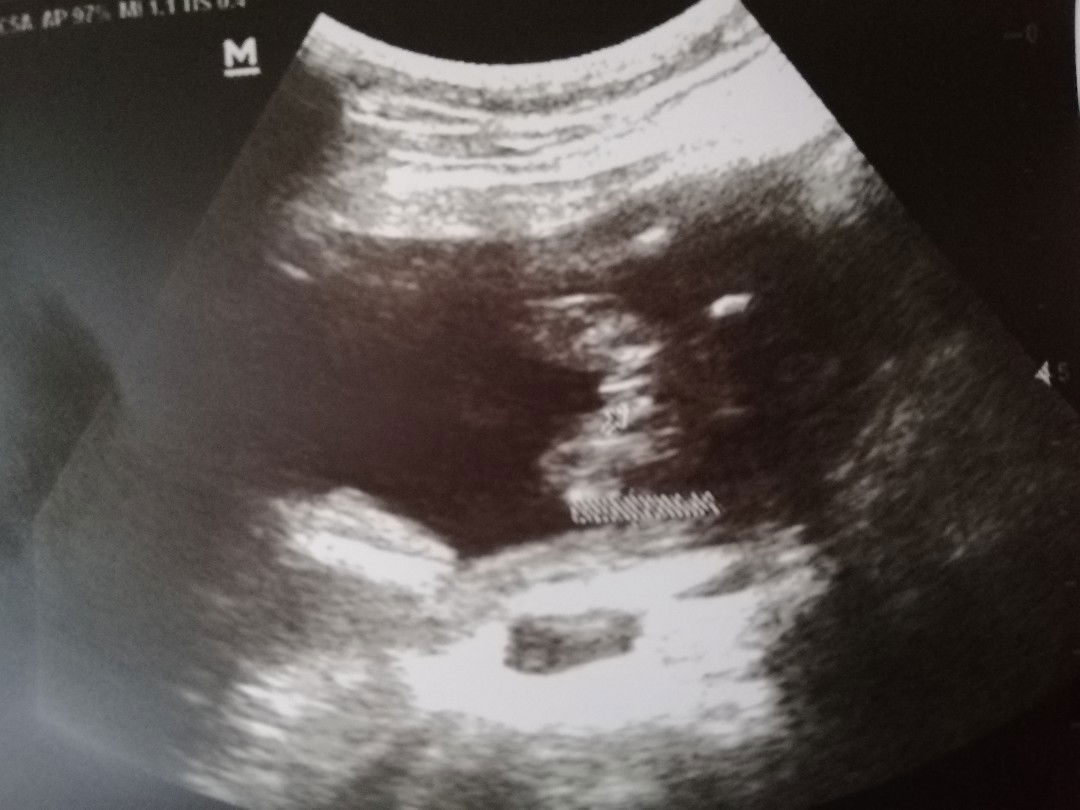

Gender

Ano po ba to baby girl or baby boy? ?

Hello po goodpm. ask ko lang po ito kung baby girl din sya talaga 😊💕

Girl. Medyo similar sa look ng ultrasound ng baby girl ko 😊

Anlabo naman. Mukang hurricane. Hehe! Ilang weeks ka na mamsh?

Girl yan may nakasulat sa ultrasound na genitalia

the hamburger sign... girl!

girl... burger eh hehehe

Girl may tatlong lines